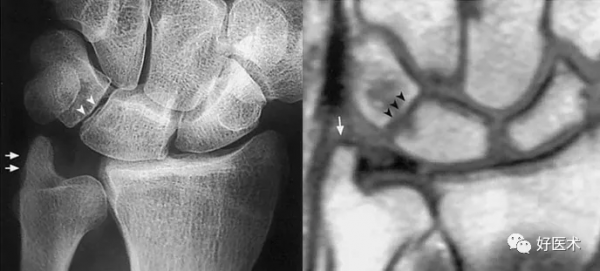

成人期腕關節正側位及舟骨蝶位片

1.舟骨 2.月骨 3.三角骨 4.豆狀骨 5.大多角骨 6.小多角骨 7.頭狀骨 8.鉤骨 9.橈骨莖突 10.尺骨莖突 11.第一掌骨基部

12.舟骨結節 黑箭:舟骨腰部 白箭:舟骨滋養血管影